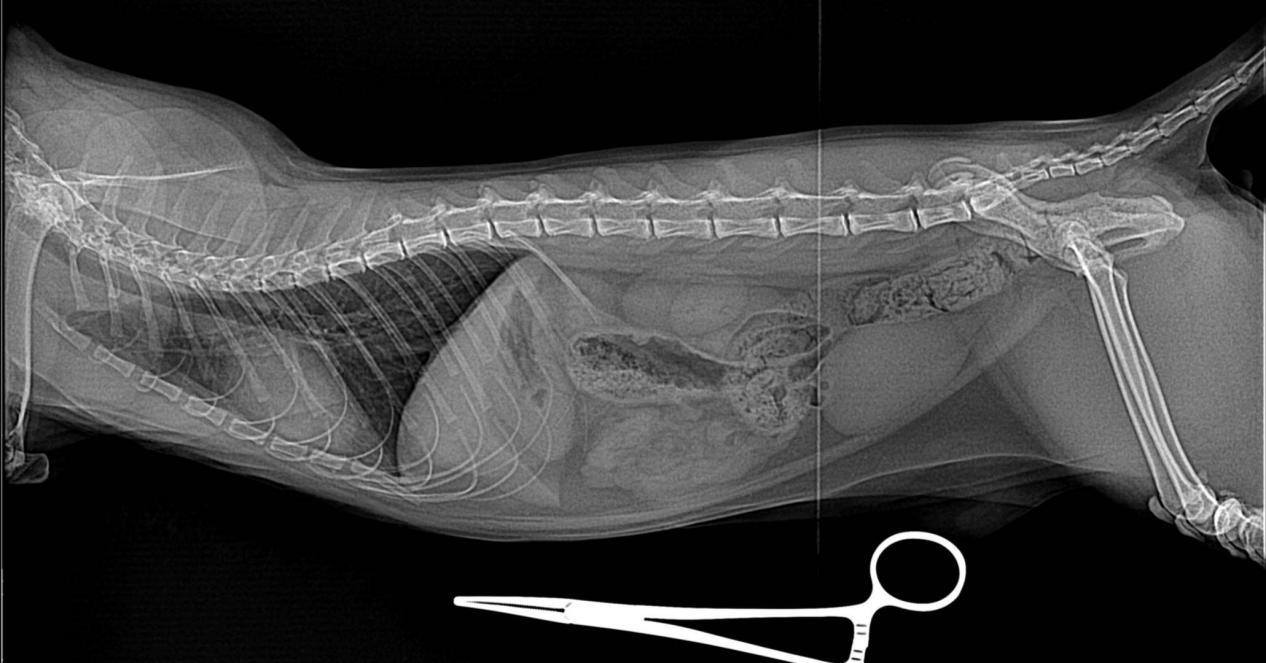

如果你家的猫咪正值青壮年,突然出现尿频、尿痛及血尿等症状,会在尿尿的时候嚎叫,或者随地乱尿的话,很大可能就是得了自发性膀胱炎。但具体还是需要去医院做尿检、影像检查来排除是否有感染、结石的可能。